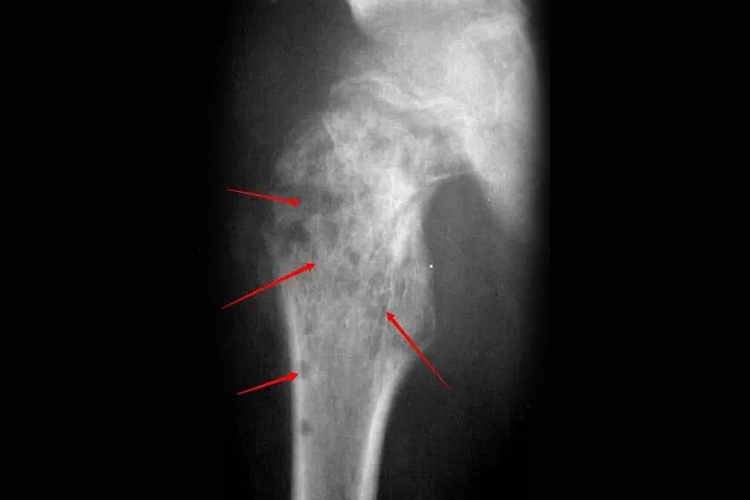

儿童骨髓炎好发于四肢骨,早期患区剧痛、呈半屈曲状,周围肌肉痉挛、疼痛,抗拒运动。局部皮温增高,有局限性压痛,肿胀不明显。数天后局部水肿,压痛加剧。如果病灶邻近关节,可有关节积液。整个骨干都被破坏后,有发生病理性骨折的可能。影像学可见骨实质的改变。此外,还可出现恶寒、高热、呕吐、惊厥等全身症状,重者可昏迷或休克。